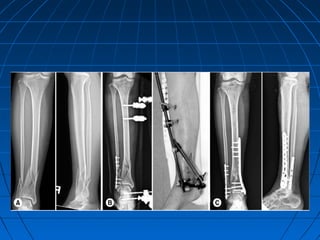

 Lateral malleolar fracturesLateral malleolar fractures

distal to syndesmosis: lagdistal to syndesmosis: lag

screw or k- wire withscrew or k- wire with

tension banding.tension banding.

 Lat. Malleolar fractures atLat. Malleolar fractures at

or above syndesmosisor above syndesmosis

require accurate reductionrequire accurate reduction

and restoration of fibularand restoration of fibular

length: combination of laglength: combination of lag

screws and plate.screws and plate.